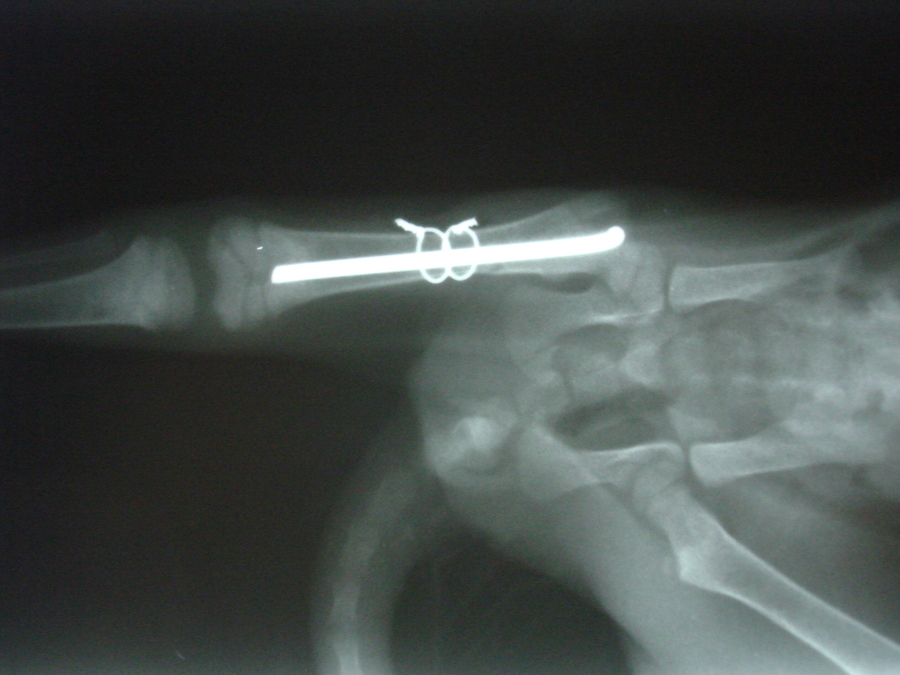

Letošní rok bylo na naše pracoviště přivedeno malé cca tříměsíční kotě, které nešťastnou náhodou vypadlo majitelům z okna. Při pádu si kotě bohužel zlomilo diafýzu stehenní kosti levé pánevní končetiny.

Fraktura stehenní kosti kotěte1

Fraktura stehenní kosti kotěte2